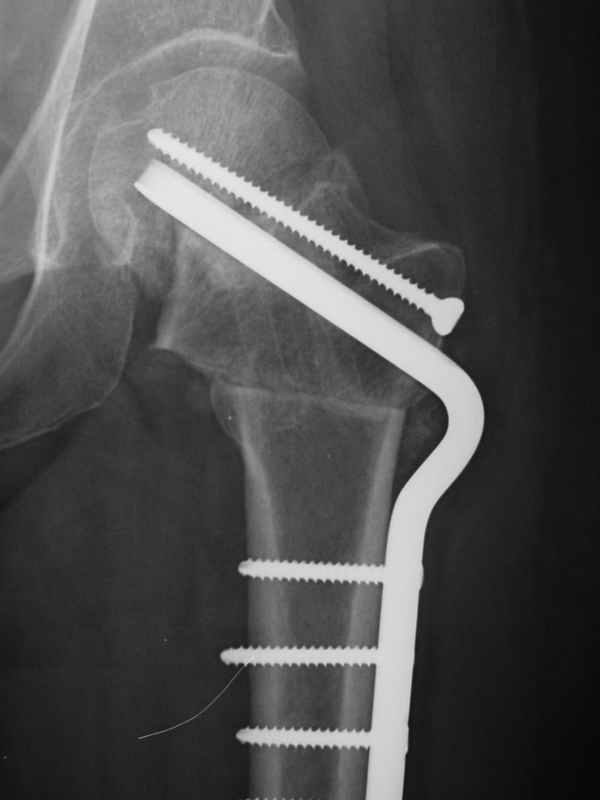

Глубокоуважаемые коллеги,Вчера обратился мужчина 31 г. Травма 2 месяца назад, лечился в одном из городов области. Был не самый тяжелый перелом таза, который проведен консервативно. С ним и связывали невозможность поднять ногу.

Однако на сегодняшнем снимке обнаружился перелом шейки бедра. Больной уже ходитс частичной нагрузкой. Учитывая срок и картину на снимке, что предпринять? У нас предложены варианты 1)не оперировать, 2)закрыто 2 спонгиозных винта, 3)вальгизирующая остеотомия. Эндопротез как-то даже в список включать пока не хочется. Какие есть соображения? Что из перечисленного или что-то другое выбрать и почему? Заранее спасибо.

Dear colleagues,A male 31 years old treated elsewhere after not severe pelvic fracture, was managed non operatively. So the injury looked as a reason of his inability to elevate the leg. However at the recent x-rays the neck fractire was found. The patient already has been walking with partial weight-bearing.Looking at the x-rays and the time since the injury, what is the optimal treatment for now? We discussed 1)leave as is, 2)2 cancellows screws as is, 3)valgus osteotomy. Total hip replacement looks unnecessary yet.What is your opinion? Which option from the listed or something else should be preferred and why?THX in advance.

А третий вариант -- поправить и фиксировать закрыто? Ну что уж так сразу -- "реконструкция"! Звучит красиво, примерно как "реформирование системы здравоохранения", а если со стороны посмотреть -- перерубание живого с внедрением инородного. Зато снимок красивый будет -- почти как заграничный в этой же дскуссии, только без суставной щели, вот в чем беда, а так все класс...

При явно выраженном варусе и флексионных состояниях после сросшихся переломов шейки бедра у молодых рекомендуется реконструктивная операция по исправлению варуса для предотвращения раннего деформирующего артроза, приводящего в результате переднего импинжмента, как показано на снимке.

Межвертельная вальгусная остеотомия представляет наименьший риск среди всех реконструктивных операции в проксимальной части бедра, создавая наилучшие биомеханические условия (увеличивается сила абдукторов, увеличивается сила суставной реакции, уменьшение рычага моментов абдукторов и уменьшение скольжения) и при меньшем риске повреждения кровоснабжения головки, где обычно в 90% случаях достигается отличный результат при применении метода для лечения ложных суставов шейки бедра.

По моему, 120 градусная угловая пластина blade plate решит все проблемы, только необходим предварительный расчет угла остеотомии, и во время фиксации пластины не забыть латерализацию бедра, иначе ось конечности от варуса перейдёт в нежелательный вальгус.

Если есть опыт межвертельной остеотомии, то лучше не придумаешь, иначе остается высокая вероятность несращения. При такой Ртг картинке после операции мы ни разу не наблюдали АНГБК, даже если открывали перелом спереди для хорошей ориентации.

the best option is valgus osteotomy with DHS and also additional canceelous screw fixation. the idea is to convert vertical shear foeces to horriszontal